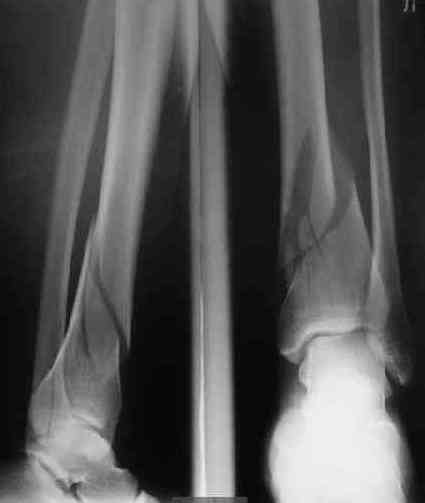

В приложении пример лечения аналогичного повреждения (плюс задний край).

> В приложении пример лечения аналогичного повреждения (плюс задний край).

Превосходно!